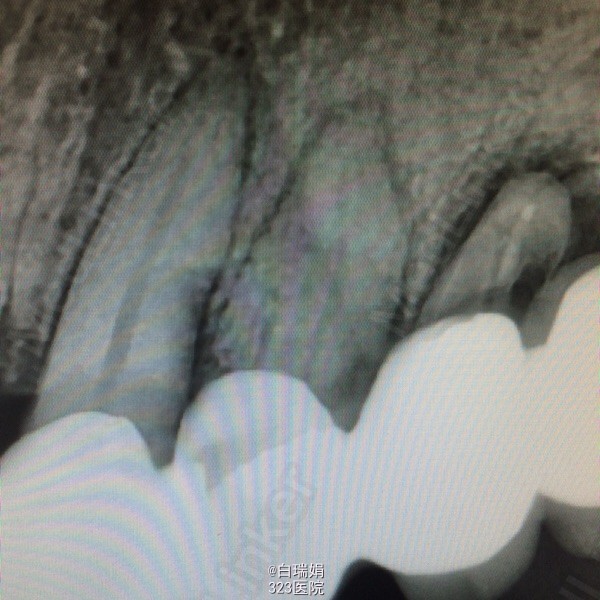

检查:左上3至左上7烤瓷联冠,松动2度,左上3、4、5、7叩诊(➕),左上7腭侧牙根吸收至根中1/3,右上4至右上7缺失,缺牙区牙槽嵴尚可,无明显骨突骨刺;X线示左上3、4、5牙周膜间隙增宽,根尖区低密度影像,左上5远中牙槽骨吸收至根中1/3,左上7牙槽骨吸收至根尖。